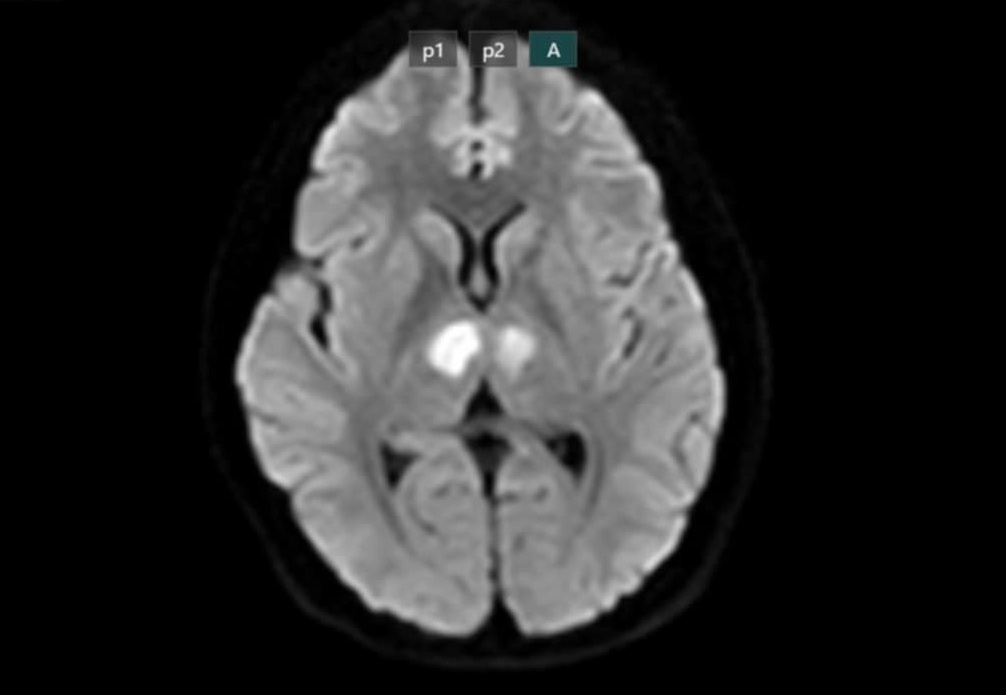

Kết quả chụp MRI cho thấy não bệnh nhân có hình ảnh tổn thương vùng đồi thị hai bên. Gia đình xin chuyển bệnh nhân sang Bệnh viện Bạch Mai để được tiếp tục điều trị. Kết quả xét nghiệm loại thuốc giảm cân bệnh nhân uống cho thấy dương tính với thành phần Sibutramin.

Não bệnh nhân bị tổn thương nặng. Ảnh: BSCC